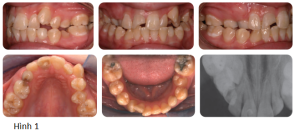

Bệnh nhân nữ 15 tuổi có sai khớp cắn hạng I trên nền xương hạng I với kích thước dọc trung bình, phức tạp bởi chen chúc nặng, R13 và R33 mọc lệch, còn nhiều răng sữa và R11 bị chấn thương (Hình 1).

- Sức khỏe răng miệng kém (các miếng trám trên những răng hàm lớn thứ nhất hàm dưới, chấn thương R11, hủy khoáng sớm ở cổ răng của những răng hàm lớn thứ nhất hàm dưới)

- Chen chúc nặng ở cả 2 cung răng

- R13 lệch (lệch trong, về phía khẩu cái) và R33 (theo đường cung răng).

- R22 cắn chéo

- Còn nhiều răng sữa